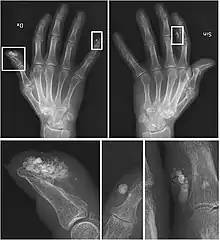

| CREST syndrome (calcinosis and sclerodactyly) | |

CREST causes thickening and tightening of the skin with deposition of calcific nodules ("calcinosis").

Sclerodactyly

Though it is the most easily recognizable manifestation, it is not prominent in all patients. Thickening generally only involves the skin of the fingers distal to the metacarpophalangeal joints in CREST. Early in the course of the disease, the skin may appear edematous and inflamed. Eventually, dermal fibroblasts overproduce extracellular matrix leading to increased tissue collagen deposition in the skin. Collagen cross-linking then causes a progressive skin tightening. Digital ischemic ulcers commonly form on the distal fingers in 30–50% of patients.[3]